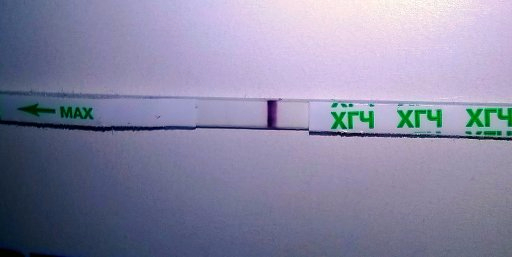

10-11дпо

Купила вчера тест мне неизвестный

Первый ответ Ева

вроде как он реагентит?

ну и видите что-нибудь?

фотокат

Эти тесты так рано не показывают. Так что реагент. Да и по фото видно, что это он

Этот тест только после задержки показывает нормально